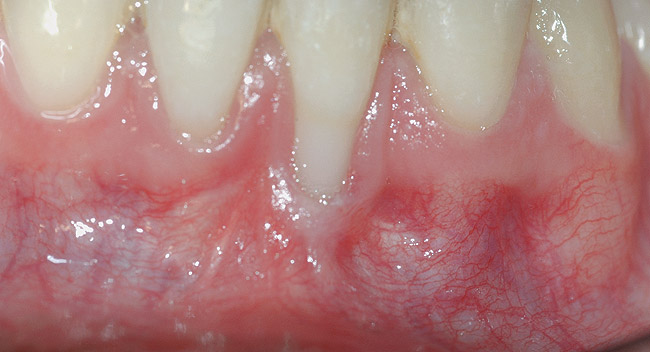

CASE 4 Fig 9. Post-orthodontic Miller Class II recession treated with surgical coverage only in spite of the incorrect inclination of the affected tooth. Clinical view immediately post-orthodontic treatment.

Figure 9

Fig 10. Same patient 5 months later showing worsening of the recession.

Figure 10

Fig 11. Same patient 1 year after connective tissue graft, showing partial root coverage.

Figure 11